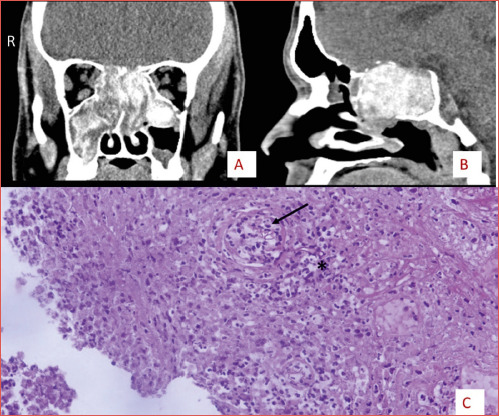

Results: The study included 26 patients. The most common forms of FRS treated by endoscopic sinus surgery was allergic FRS (AFRS). The fungus identification rate varied between entities, and was 72.2% in AFRS and 33.3% in fungal ball specimens. The common species seen in AFRS isolates were Cladosporium spp. (38.5% of isolated) and dematiaceous molds in the same percentage, while the remainder of the cultures were hyaline moulds. CT scan can be very helpful in diagnosing FRS and sometimes even in differentiating between different entities. Treatment of FRS should be tailored for each entity. Postoperative medical treatment in AFRS should consider potential advancements described in the literature.

Abstract Image